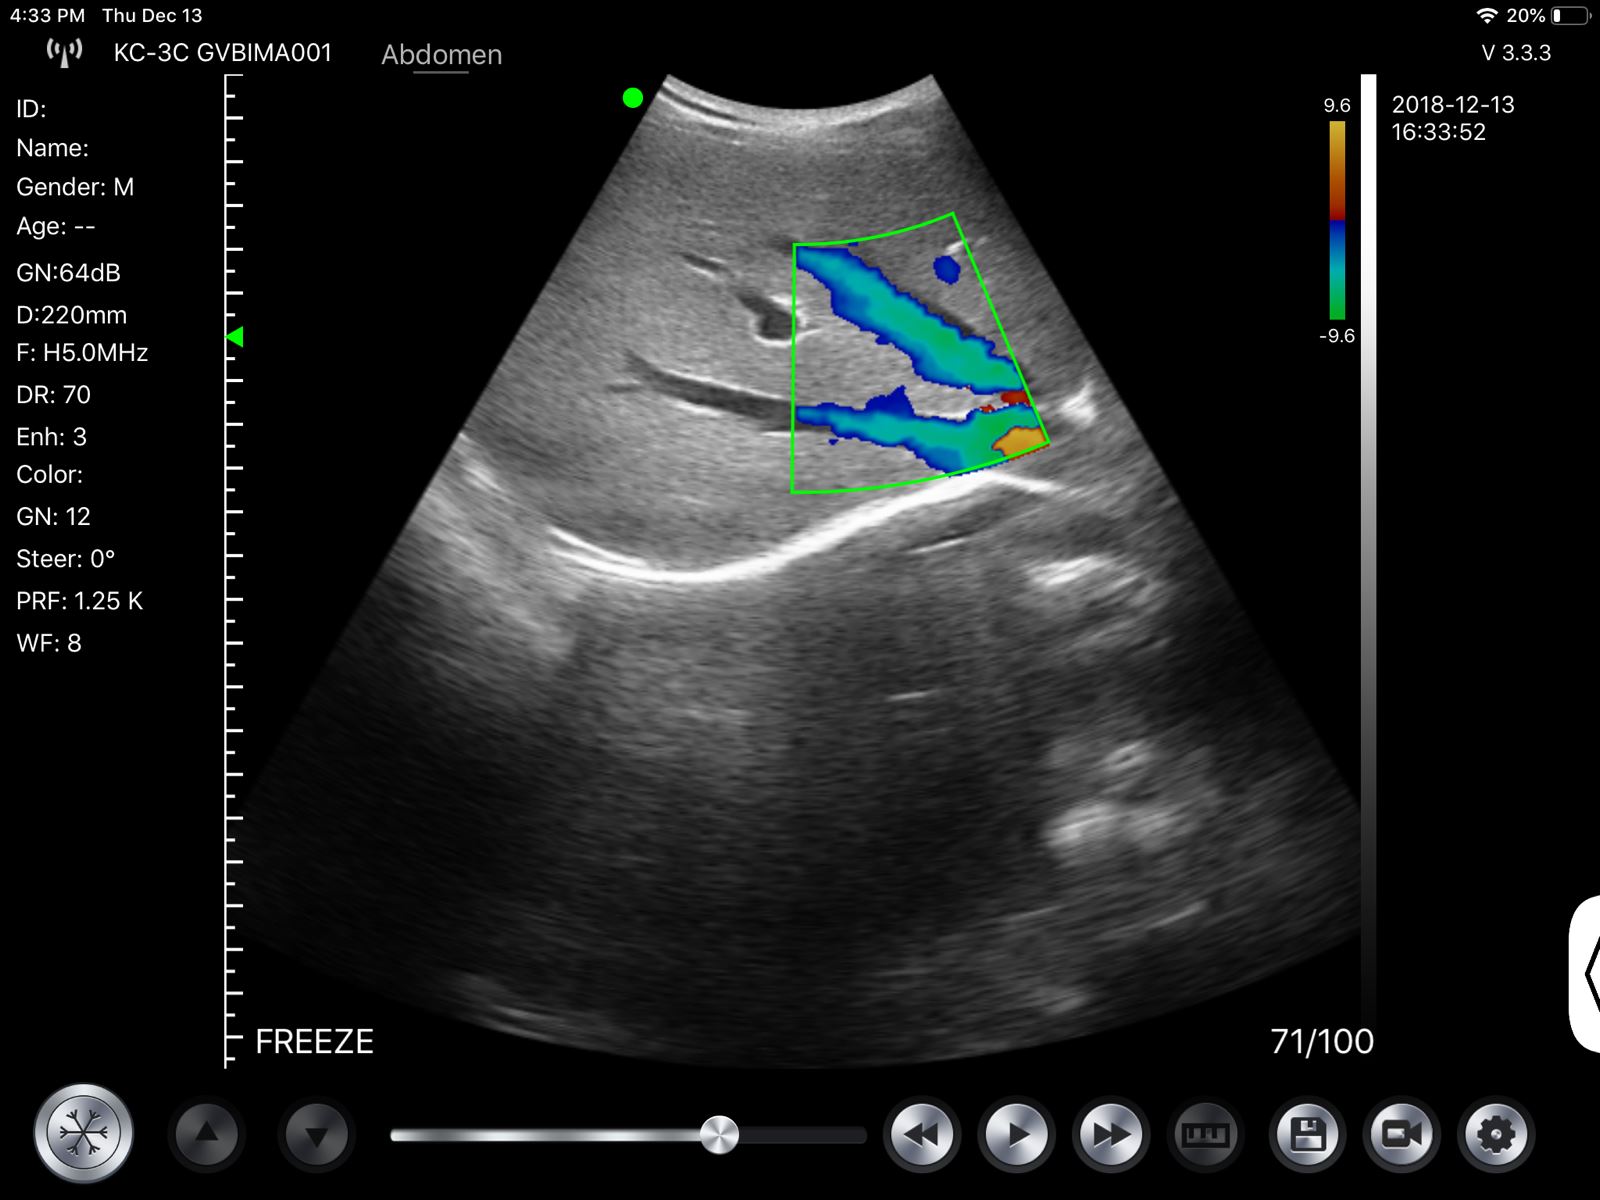

Wireless Fetal Doppler Convex Probe Veterinary Ultrasound for iPad, iPhone App

Wireless Wifi Doppler Convex Array Probe Type Ultrasound Scanner. This wireless Wifi Convex Array Probe with integrated ultrasound circuit boards inside, then realize the functions of an ultrasound scanner. It can be used at many occasions such as In emergency, clinical, and hospital. In addition, CT is easy to operate because it has a unique design with three buttons which is a portable ultrasound machine.

- Display Mode: B, B/M, Color, PW, PDI